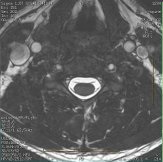

Figure 1. FIESTA-C cervical spine